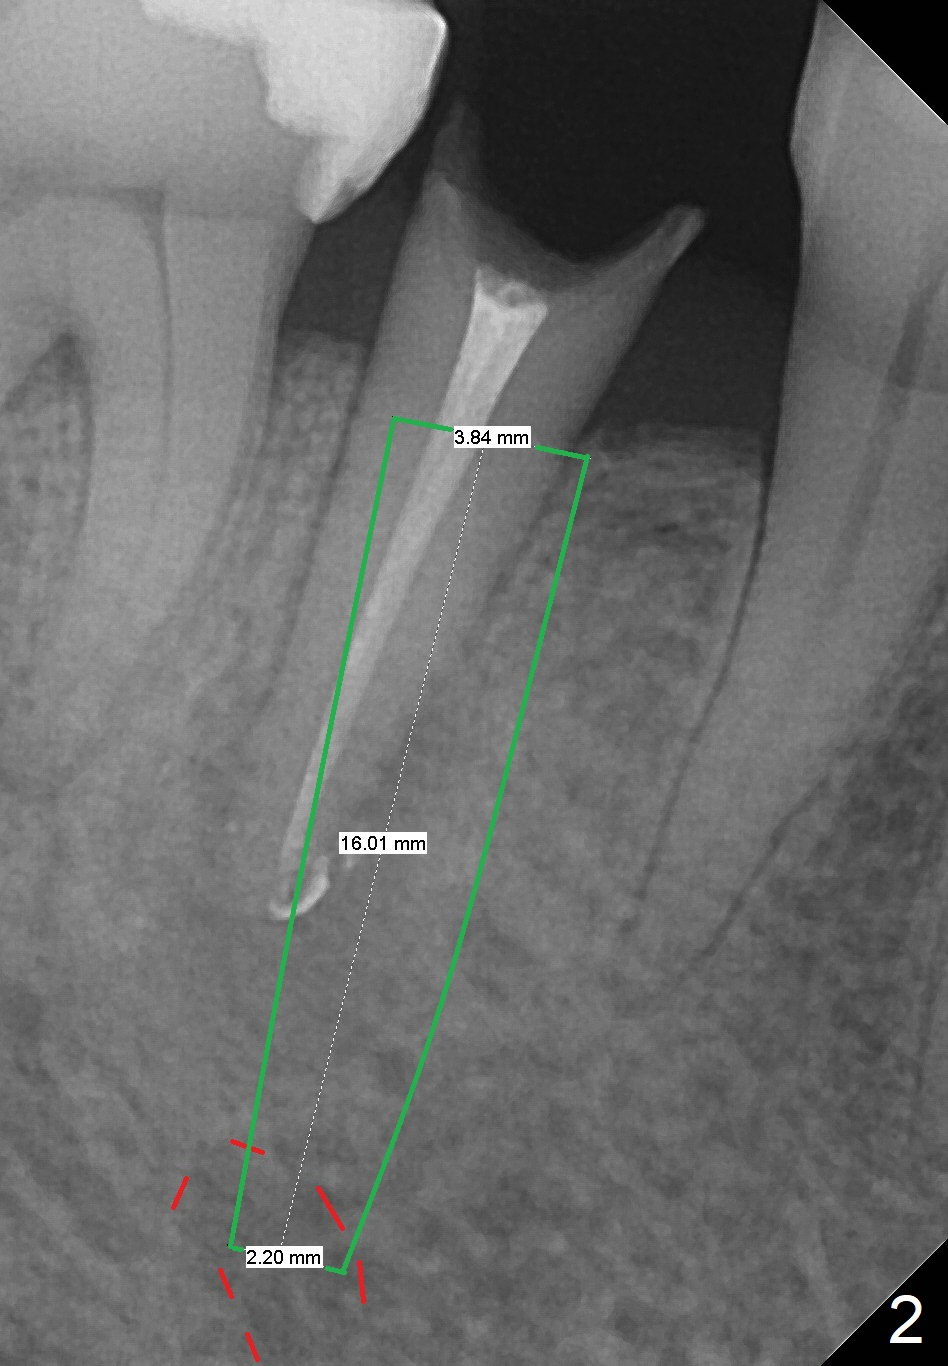

A 67-year-old woman fractures the tooth #29 three months post RCT.  There is persistent periapical radio-lucency (Fig.1 yellow dashed line), which is close to the Mental Loop (red dashed line).  Since the root of the affected tooth deviates distal, osteotomy will be established mesial (Fig.2).  To reduce the chance to injury the buccally located loop, the osteotomy should be as lingual as possible.  Initial depth will be 15 mm (shy of the Loop, bone level, 18-19 mm gingival level) with 2 mm drill, followed by the marked parallel pin.  If primary stability cannot be achieved, place a long implant as indicated in Fig.2 as long as the osteotomy remains lingual.